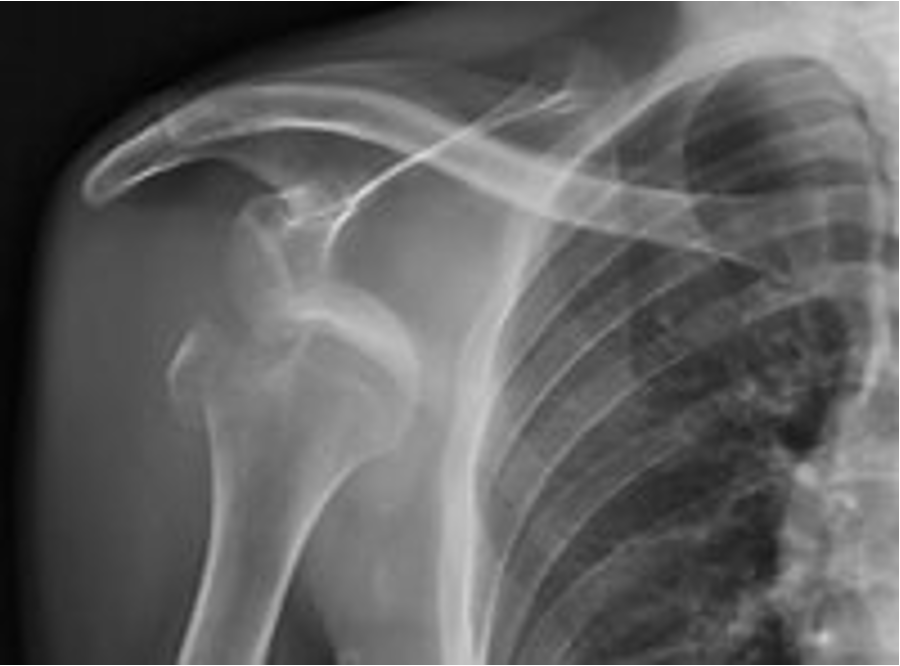

A 55 yo window cleaner falls from a ladder injuring right shoulder.

1. What is Diagnosis?

2. Which tendons attach to the fractured part?

3. Which nerves or vessels are most susceptible to damage in this type of injury?

1. Fracture/dislocation Right shoulder – anterior. Greater tuberosity/tubercle fracture.

2. Supraspinatus – greater facet attachment

Infraspinatus – middle facet attachment

Teres minor - inferior facet attachment

3. Axillary nerve & posterior and anterior circumflex humeral vessels (Quadrangular space)

Radial nerve and brachial plexus